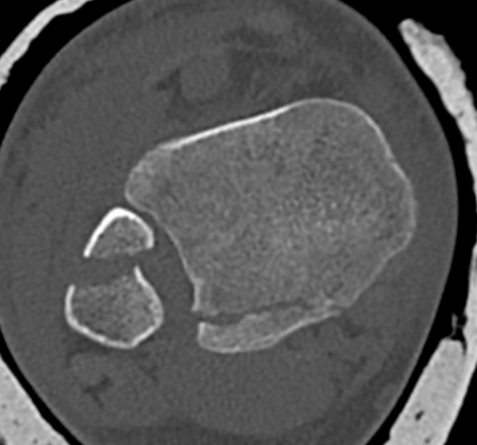

Mason and Malloy Classification

CT scan critical to classify and guide treatment / approach

| Type I | Type IIA | Type IIB | Type III |

|---|---|---|---|

| Avulsion of the PITFL |

Posterolateral fragment Volkmann fracture |

Posteromedial & posterolateral fragments Volkmann plus secondary fracture line |

Large coronal plane fragment Plafond fracture |